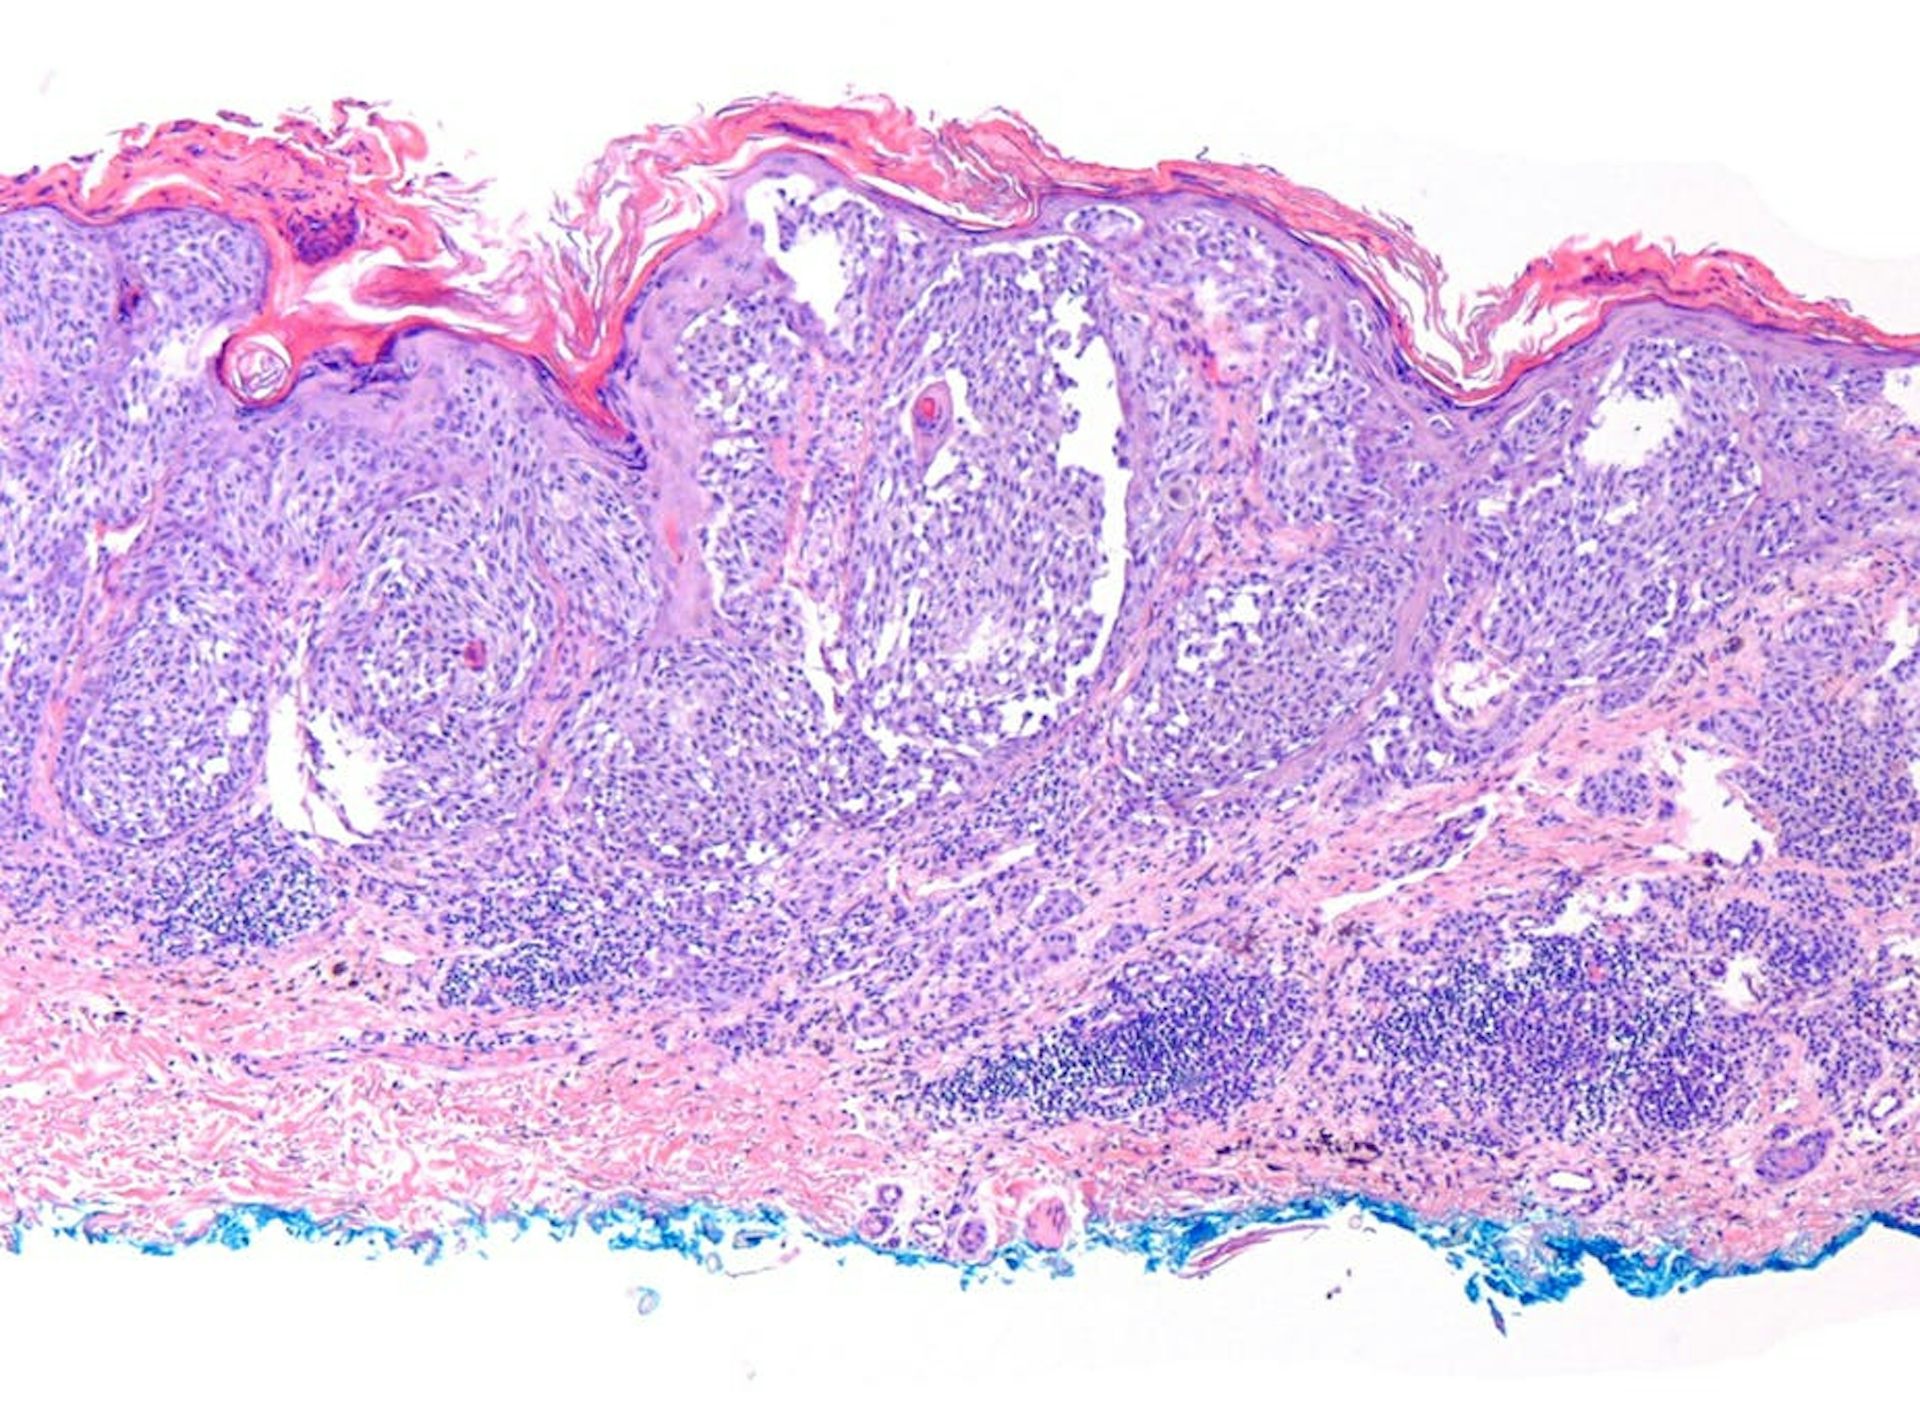

В 1978 году Кларк с соавторами впервые описали множественные наследственные невусы, являющиеся предшественниками меланомы и обозначили эту ситуацию как «В-К моль синдром». Гистологически эти образования, которые в дальнейшем стали называться диспластическими невусами, представляли собой атипическую меланоцитарную гиперплазию, лимфоидную инфильтрацию, нежную фиброплазию и новообразованные кровеносные сосуды.

При гистологическом исследовании диспластических невусов авторы обнаружили 2 типа нарушения роста внутриэпидермальных меланоцитов, наиболее частый тип – лентигинозная меланоцитарная дисплазия (ЛМД) – наблюдался во всех диспластических образованиях и напоминал изменения, происходящие в lentigo simplex.

Второй тип нарушения роста – эпителиоидно-клеточная меланоцитарная дисплазия – был найден в 2х образованиях в дополнение к лентигинозной меланоцитарной дисплазии и напоминал классическую поверхностно-распространяющуюся меланому.

В 1982 году профессор МНИОИ им. П.А.Герцена З.В. Гольберт впервые выделила 3 степени развития лентигинозной меланоцитарной дисплазии (ЛМД). При 1 степени отмечалось увеличение числа меланоцитов в базальном слое эпидермиса и некоторая их атипия. При 2 степени имелись более выраженная пролиферация меланоцитов, местами полностью замещающих базальный ряд кератиноцитов, и нарастание признаков их анаплазии. 3-я степень ЛМД, при которой имеется тенденция к врастанию меланоцитов в выше расположенные слои эпидермиса и вглубь, в сосочковый слой дермы, приближается к картине меланомы in-situ.

25.11.15 произведено иссечение образования, отступя от видимых границ 2,0 см. Гистологическое исследование №82986: в зоне пятна, в центре кожного лоскута картина эпителиоидной меланоцитарной дисплазии атипического характера, в одном из участков крайне подозрительная по переходу в меланому. Пациентка выписана из стационара с диагнозом «Пигментный невус кожи левой лопаточной области».

Гистологический препарат был консультирован в МНИОИ им. П.А.Герцена к.м.н. Ягубовой Э.А., заключение: эпителиоидно-клеточная пигментная неизъязвленная лентиго-меланома in-situ на фоне смешанного диспластического невуса, с умеренной лимфоидно-плазмоклеточной инфильтрацией в основе. Удалено в пределах здоровых тканей.

01.17. произведена эксцизионная биопсия образования, отступая от границ 0,5 см. Гистологическое исследование, проведенное в МНИОИ им. ПА.Герцена (Ягубова Э.А.) выявило смешанный пигментный невус с тяжелой (3 степени) меланоцитарной ленигинозной дисплазией, удаленный в пределах здоровых тканей. В основе – выраженная лимфоидно-плазмоклеточная инфильтрация.